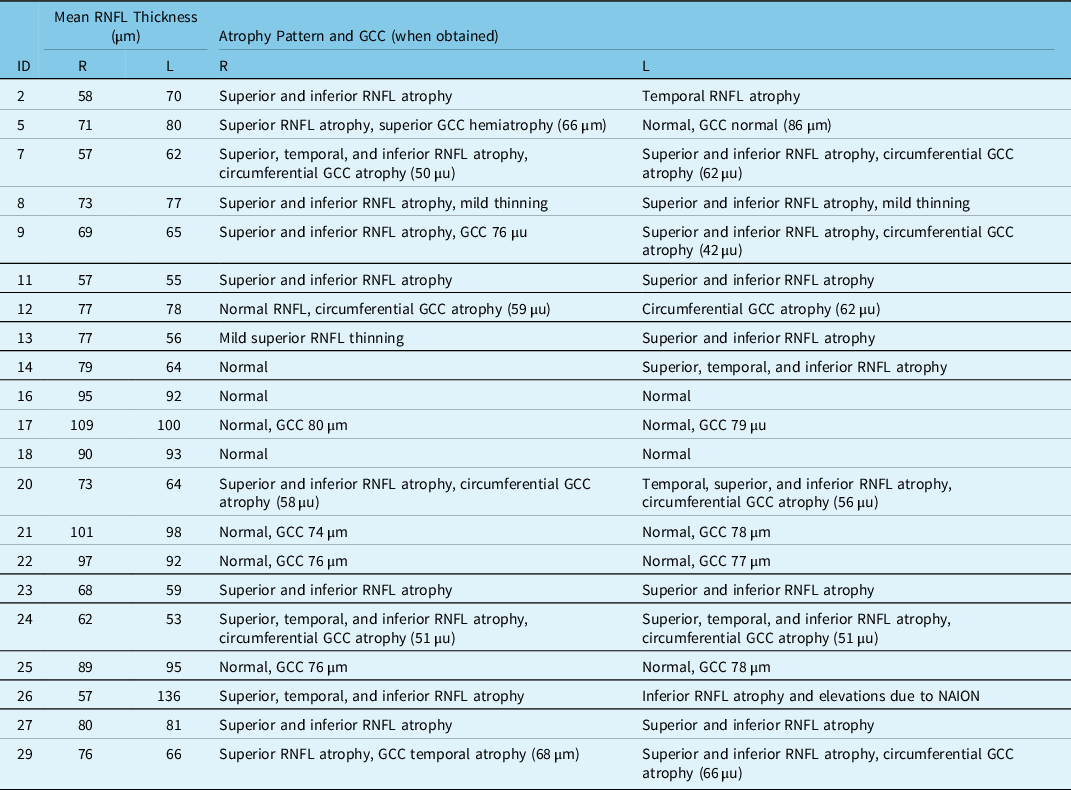

Table 2: Summary of most recent available OCT results

GCC = Ganglion cell complex; L = Left; R = Right; RNFL = Retinal nerve fiber layer.